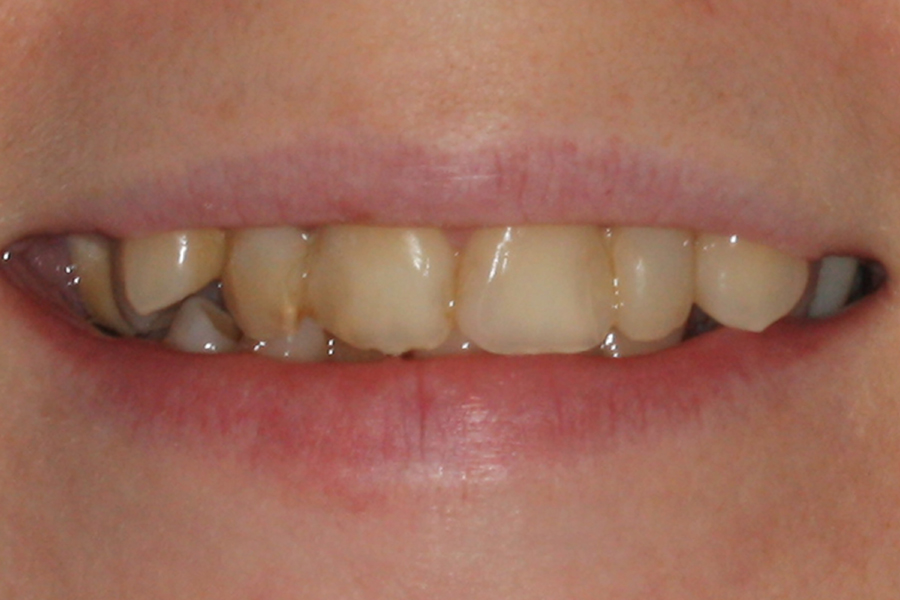

Kompleksowe leczenie zachowawczo-ortodontyczne

Młoda pacjentka zgłosiła się do naszego gabinetu celem wykonania kompleksowego leczenia zachowawczo-ortodontycznego. Oprócz problemów natury ortodontycznej stwierdzono złą higienę jamy ustnej oraz liczne potrzeby leczenia zachowawczo-endodontycznego. Po wnikliwej analizie telerentgenowskiej oraz analizie modeli zadecydowano o ekstrakcji 2 zębów w łuku dolnym (kła po stronie lewej oraz pierwszego przedtrzonowca po stronie prawej). Plan leczenia obejmował ponadto zamknięcie łuku po brakujących zębach w łuku górnym. Leczenie aktywne trwało 2 lata i 8 miesięcy. W czasie jego trwania pacjentka była regularnie poddawana zabiegom higieny profesjonalnej celem eliminacji zapaleń przyzębia brzeżnego. Po leczeniu aktywnym zastosowano leczenie retencyjne w postaci retainera stałego w żuchwie oraz szyny retencyjnej w łuku górnym.